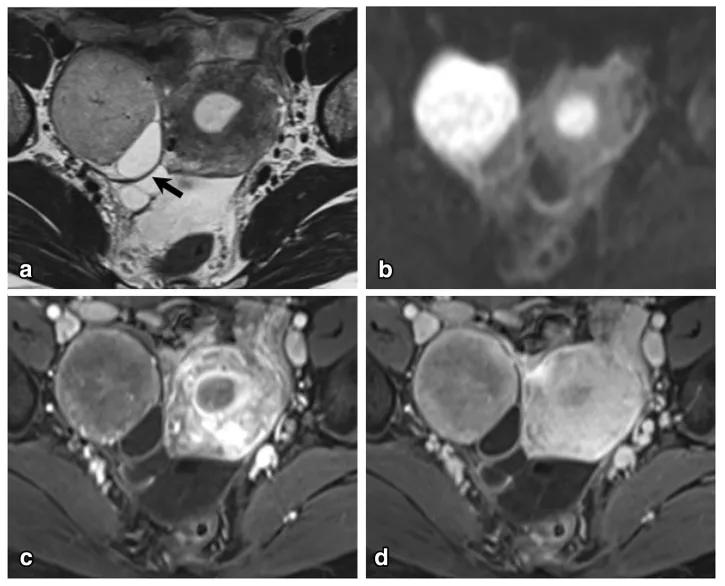

女,64 岁,雌激素升高,卵巢子宫内膜样癌。卵巢肿物由三部分构成,偏右侧是囊性成分;中间部分(箭头)T2WI 及 DWI 呈低信号(a 及 b),增强扫描明显强化(c 增强早期,d 增强晚期);偏左侧部分 T2WI 稍高信号,DWI 高信号,增强扫描明显强化。HE 染色显示中间部分肿物由功能性纤维间质构成(图 e)。HE 染色肿瘤左侧部分显示子宫内膜样癌与性索间质肿瘤类似。矢状位显示子宫体积增大(图 g)

女,47 岁,卵巢子宫内膜样癌。右侧卵巢异常信号肿物,T2WI 混杂稍高及高信号(图 a),DWI 高信号(图 b),增强扫描不均匀强化(图 c)。肿物内见条片状裂隙样异常信号(箭头),T2WI 呈高信号、DWI 低信号、增强扫描未见强化。